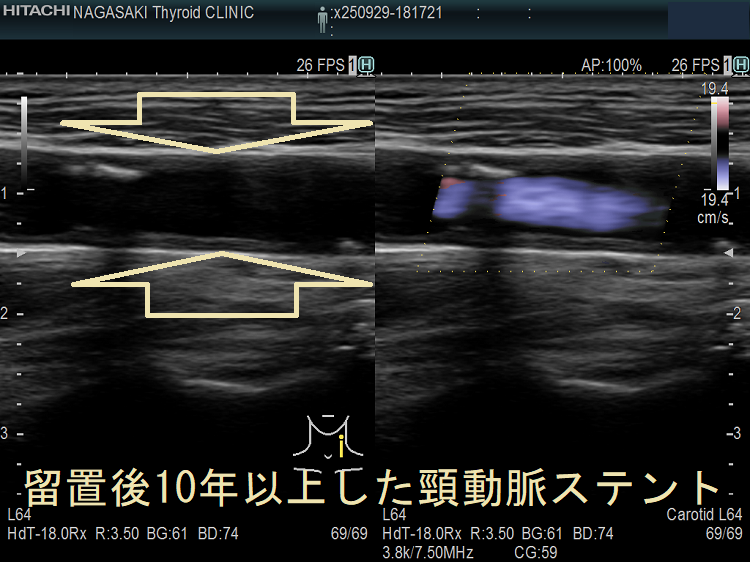

頸動脈ステントを留置した患者の甲状腺 超音波(エコー)画像;写真の頸動脈ステントを留置した患者は、甲状腺機能低下症/橋本病により動脈硬化が進行していました。(甲状腺と動脈硬化)

甲状腺機能低下症/潜在性甲状腺機能低下症/橋本病、糖尿病などでは動脈硬化が進み、頚動脈プラークにできた血栓が脳へ流れて脳梗塞。最悪、頚動脈自体の閉塞も。血管エコーでプラークを探す。動脈硬化血管は硬くもろく、大動脈では血圧に負けて大動脈瘤に。頸動脈閉塞度70%以上でカテーテル手術、ステント留置。時間が経つとステント上に新たなプラーク形成。内頸動脈ステント留置時、ガイドワイヤーで外頸動脈枝の上甲状腺動脈穿孔おこした報告あり。コレステロール/脂質塞栓が、網膜動脈を完全/不完全閉塞すると黄色斑(ホレンホースト斑)が生じる。